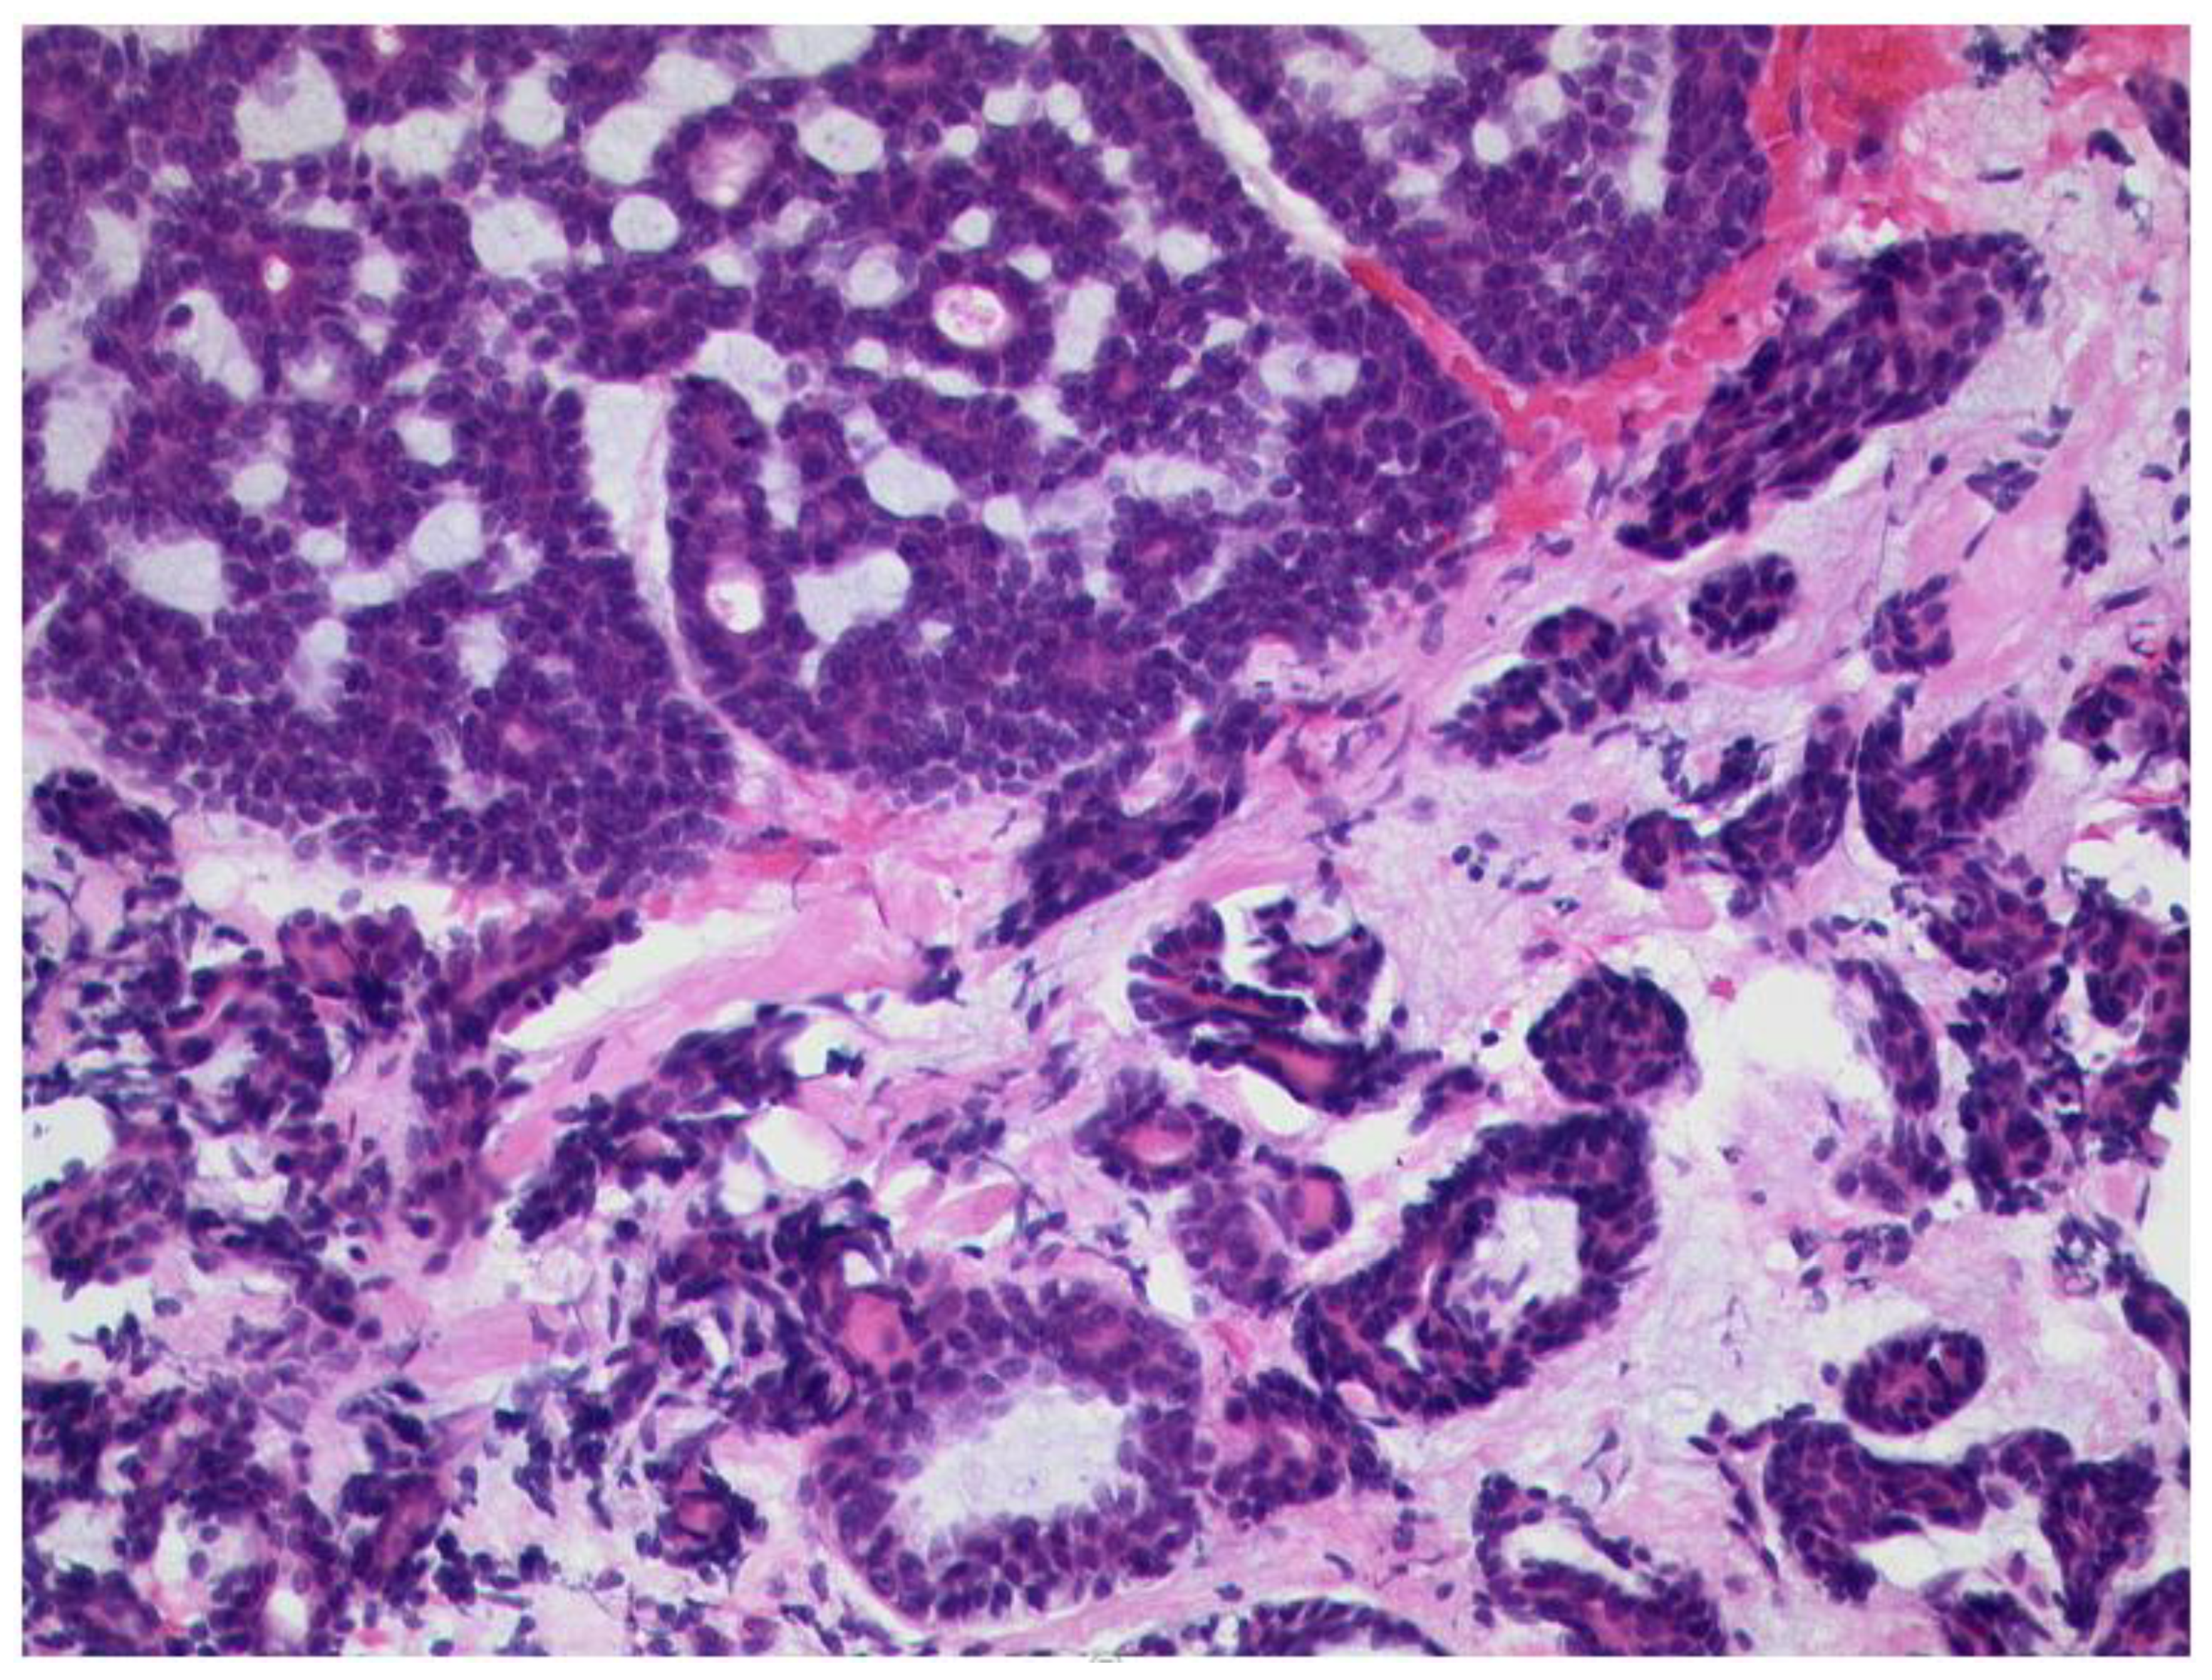

3.6.2. Rhabdomyosarcoma